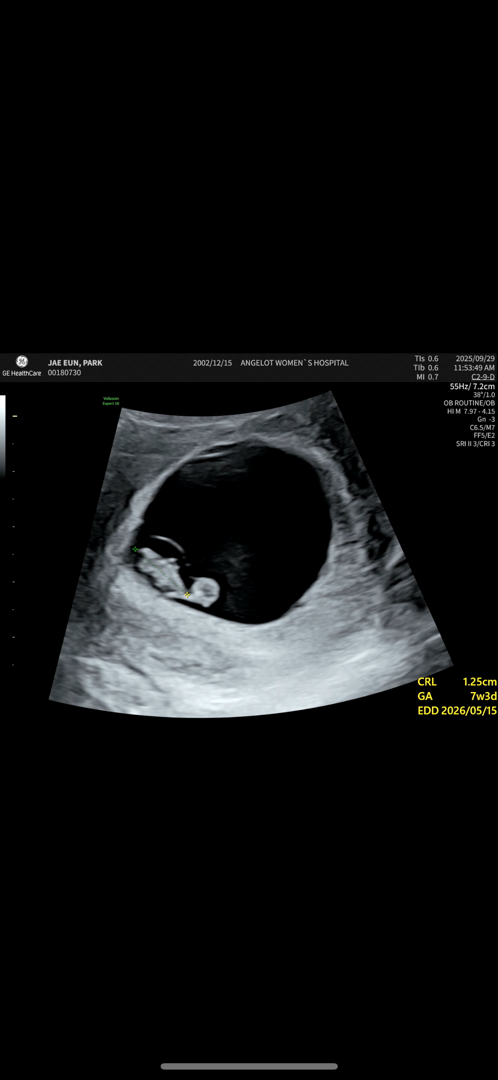

7주차 번데기

젤리곰 기대했는데 번데기가 있어요 ㅋㅋㅋㅋㅋㅋ 9주차에가면 젤리곰은 이미 지나있겠죠??